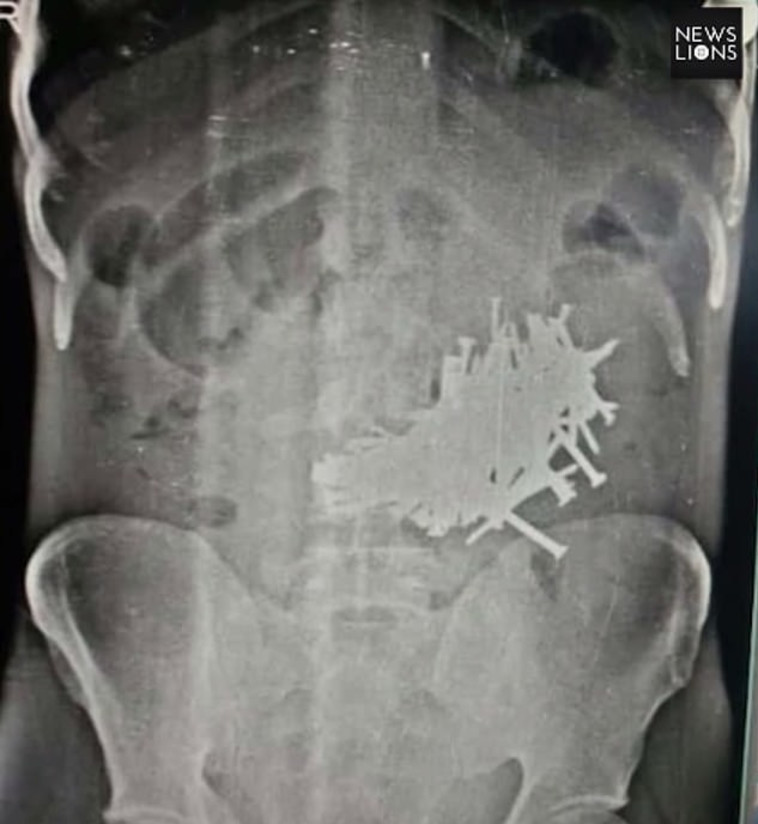

צילום הרנטגן שחשף את המסמרים בבטנו. צילום: כלי התקשורת המקומיים

גבר בלע יותר מ-116 מסמרים - ושרד: "יש לו הרבה מזל"

הסתיר ממשפחתו את הרגלי האכילה המסוכנים שלו וכמעט שילם על כך בחייו: "אם הם היו מנקבים את איבריו זה היה יכול להיות קטלני"